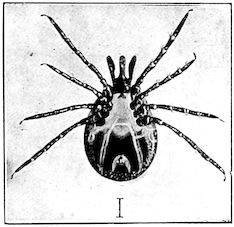

Fig. 1.—Rachitis in a young goat.